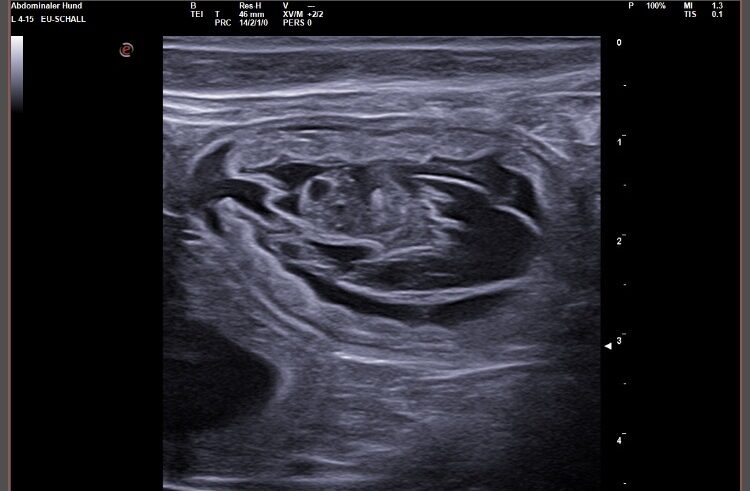

Wir waren erfolgreich und konnten Fruchtanlagen mit schlagenden Herzen sehen. Wir gehen zum aktuellen Zeitpunkt wieder von einem größeren Wurf aus. Daykos und Dorias Rendevouz war also sehr vielversprechend!

Hier zeigen wir euch einige der kleinen gefüllten Fruchtblasen mit Inhalt und schlagenden Herzen. Da wir kurz vor Ostern mit der Geburt rechnen, nennen wir sie „Ostereier“ 🙂